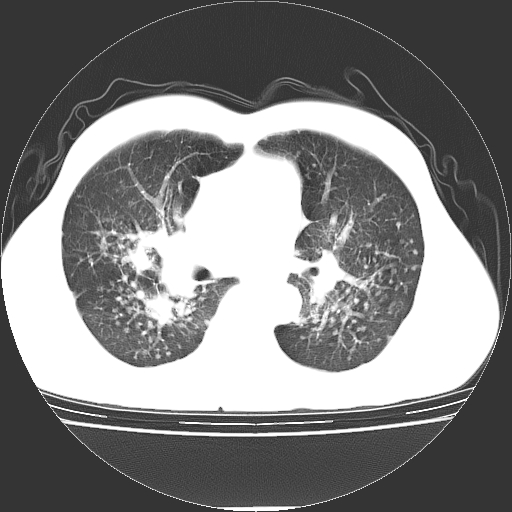

以下是引用yangyudong333在2008-4-29 5:38:00的发言:[br]比较典型的矽肺结节.支持[br]诊断依据:[br] 1.x线表现:[br] ①典型矽肺为多发直径 1~3mm 小结节,即矽结节,由胶原纤维和硅尘构成,可融合成团块,好发于上肺。[br] ②团块周围常有肺大泡。[br] ③胸内淋巴结增大、钙化。如肺门淋巴结呈蛋壳样钙化有助于与其他尘肺区别。[br] ④胸膜常广泛粘连、增厚。[br] 2.ct表现[br] ①两肺散在大小较为一致的小结节影,其密度较高,边界清楚。[br] ②小结节可融合为较大团块影,直径约 1cm ,甚至可达 10cm以上,易发生在上叶。[br] ③小结节周围常并有小叶中心气肿或弥漫性肺气肿。

以下是引用liuyue在2008-4-28 22:30:00的发言:[br]比较典型的矽肺结节.[br]请结合临床及化验除外矽肺合并肺结核之可能.